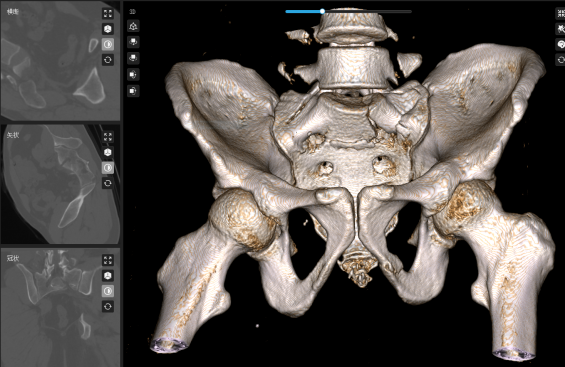

术前:骶骨骨折,骶神经受压。

术前,叶军博士将患者的骨盆骶骨CT数据导入骨科机器人数字平台,进行三维重建和精准分析。通过数字化技术,医生能够清晰看到骶骨骨折移位及骶前孔受压的具体情况:骶骨体骨折塌陷,左侧骶骨翼受侧方挤压,骶1骶前孔前方受碎骨块压迫。

*3D透视骨骼迷宫:第一时间输入CT数据至骨科机器人数字平台,3D重建精准锁定碎骨位置;